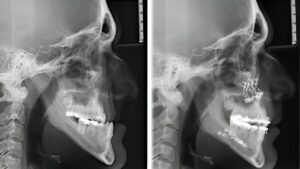

Cuidar da saúde bucal é essencial para manter um sorriso saudável e prevenir complicações futuras. Muitas pessoas não percebem a importância de consultar o dentista